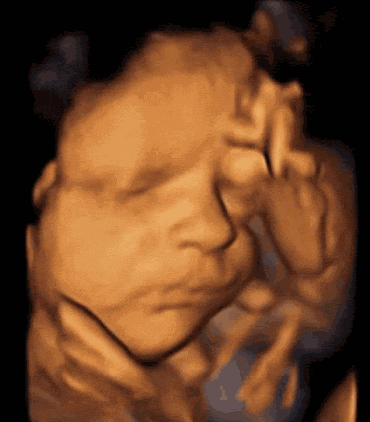

- 想知道宝宝的发育情况? 想亲眼目睹宝宝在肚子里的一颦一笑? 那就做四维彩超吧, 美国GE-E8四维彩超仪, 以全球化的视野, 见证生命成长每一刻, 不仅可以实现与宝宝的清晰会面...【阅读全文】

- 如今随着四维彩超的愈发普及, 跟宝宝的第一次会面 再也不用苦苦等待漫长的十个月啦! 四维彩超可自动为胎儿 进行深宫照相及生成动态图像, 让准爸妈能清看清胎儿的五官和动作...【阅读全文】

- 很多孕妈都以为四维彩超是彩色的,其实并非如此,四维彩超其实是土黄色的;不过相对于普通的B超以及三维彩超,四维彩超更清晰而且能看到胎儿的各种运动,比如吐舌头,捂眼睛,...【阅读全文】